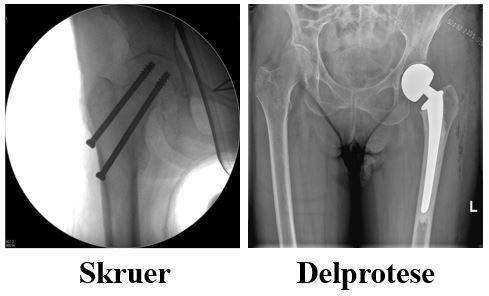

Der findes 3 forskellige typer hoftebrud. Vi har sat kryds ved den type brud du har.

Ved brud på lårbenshalsen samles bruddet med skruer eller lårbenshoved fjernes og erstattes med en hofteprotese/kunstigt hofteled.

Behandling af dit brud afhænger af bruddets type.

Der er i dit tilfælde anvendt den operationsform, som er afkrydset, se billeder på næste side. Forskellige brud i hoften behandles med skruer, med halvprotese, med glideskrue, med et marvsøm og skruer.